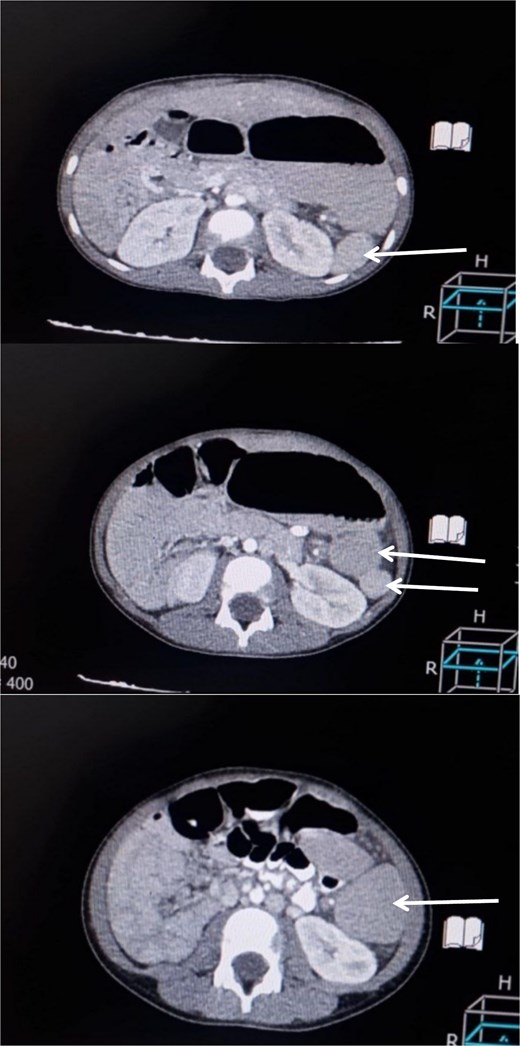

A 6-year-old boy presented with a 2-day history of abdominal pain, vomiting, and diarrhea. The pain was of sudden onset, severe, intermittent, mainly in the umbilical region, not radiating anywhere, with no aggravating or relieving factors. It was associated with non- bilious vomiting of small amounts of food contents, in addition to small amounts of diarrhea not containing mucus or blood. Upon admission, the patient looked unwell but not febrile. His pulse rate was 100 beats/min, and the respiratory rate was 24 breaths/min. Abdominal examination revealed a firm, non-tender mass, ~8 × 4 cm in diameter with a smooth surface, palpable just left of the umbilicus. Laboratory investigations were unremarkable. An abdominal ultrasound was performed initially that showed a well-defined, 10 × 4 cm homogenous mass, seen at the midline and extending to the left of the midline suggestive of an enlarged spleen. As the ultrasound was inconclusive, a contrast-enhanced CT abdomen was obtained, which demonstrated multiple spleen-like densities in the left upper and lower abdominal quadrants with minimal free fluid in the left iliac fossa (Fig. 1).

Contrast-enhanced CT scan of the abdomen demonstrating multiple spleen-like densities (arrows) can be seen in the left upper and lower quadrants of the abdomen.

Imaging modalities play a central part in the diagnostic workup. While ultrasound can suggest the presence of a mass or splenomegaly, contrast-enhanced CT is best suited to describe accessory spleens and signs of torsion in the form of a twisted vascular pedicle or an infarcted spleen [1–4, 13]. A definitive diagnosis, however, is often made intraoperative, as in this case where exploratory laparotomy revealed a twisted and infarcted splenule with an associated long vascular pedicle. The surgery involved detorsion and resection of the involved splenule with preservation of the intact accessory spleens and the native spleen in accordance with modern guidelines to avoid the risk of overwhelming post-splenectomy infection, particularly in children [1–4, 8, 13].